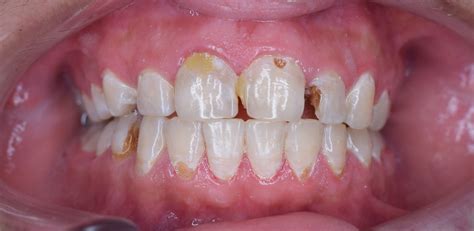

Recognizing the signs of tooth decay front teeth problems early can save you from invasive dental procedures. The process typically begins with white spots, which indicate demineralization, followed by brown or black spots as the decay deepens. Symptoms to watch for include:

- Visible white, yellow, or brown spots on the surface of the teeth.

- Small holes or pits (cavities) on the surface of the enamel.